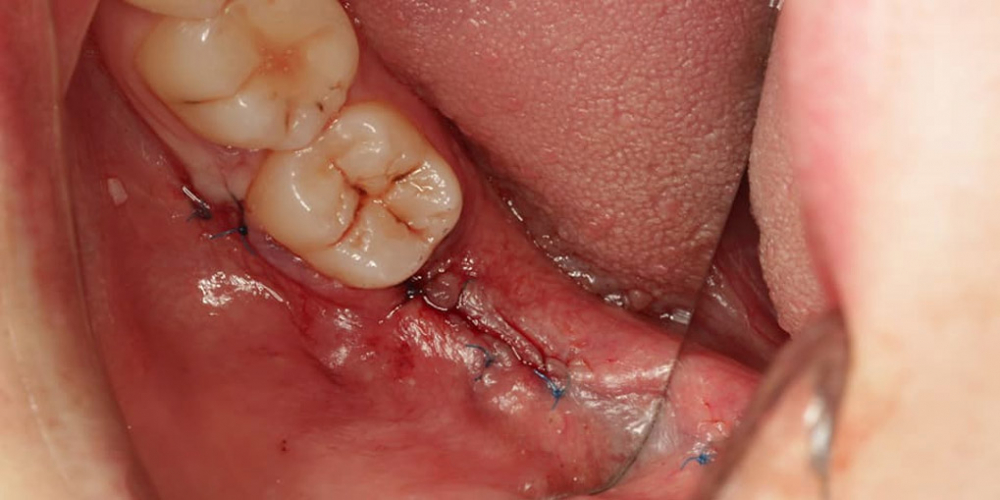

Удаление зуба мудрости сообщающегося с нижнечелюстным каналом: фотографии до и после.

Удаление ретинированого зуба 4.8 сообщающегося с нижнечелюстным каналом.

Хирургия, Консультация хирурга, Удаление зуба мудрости, Сложное удаление, Удаление ретинированного зуба.